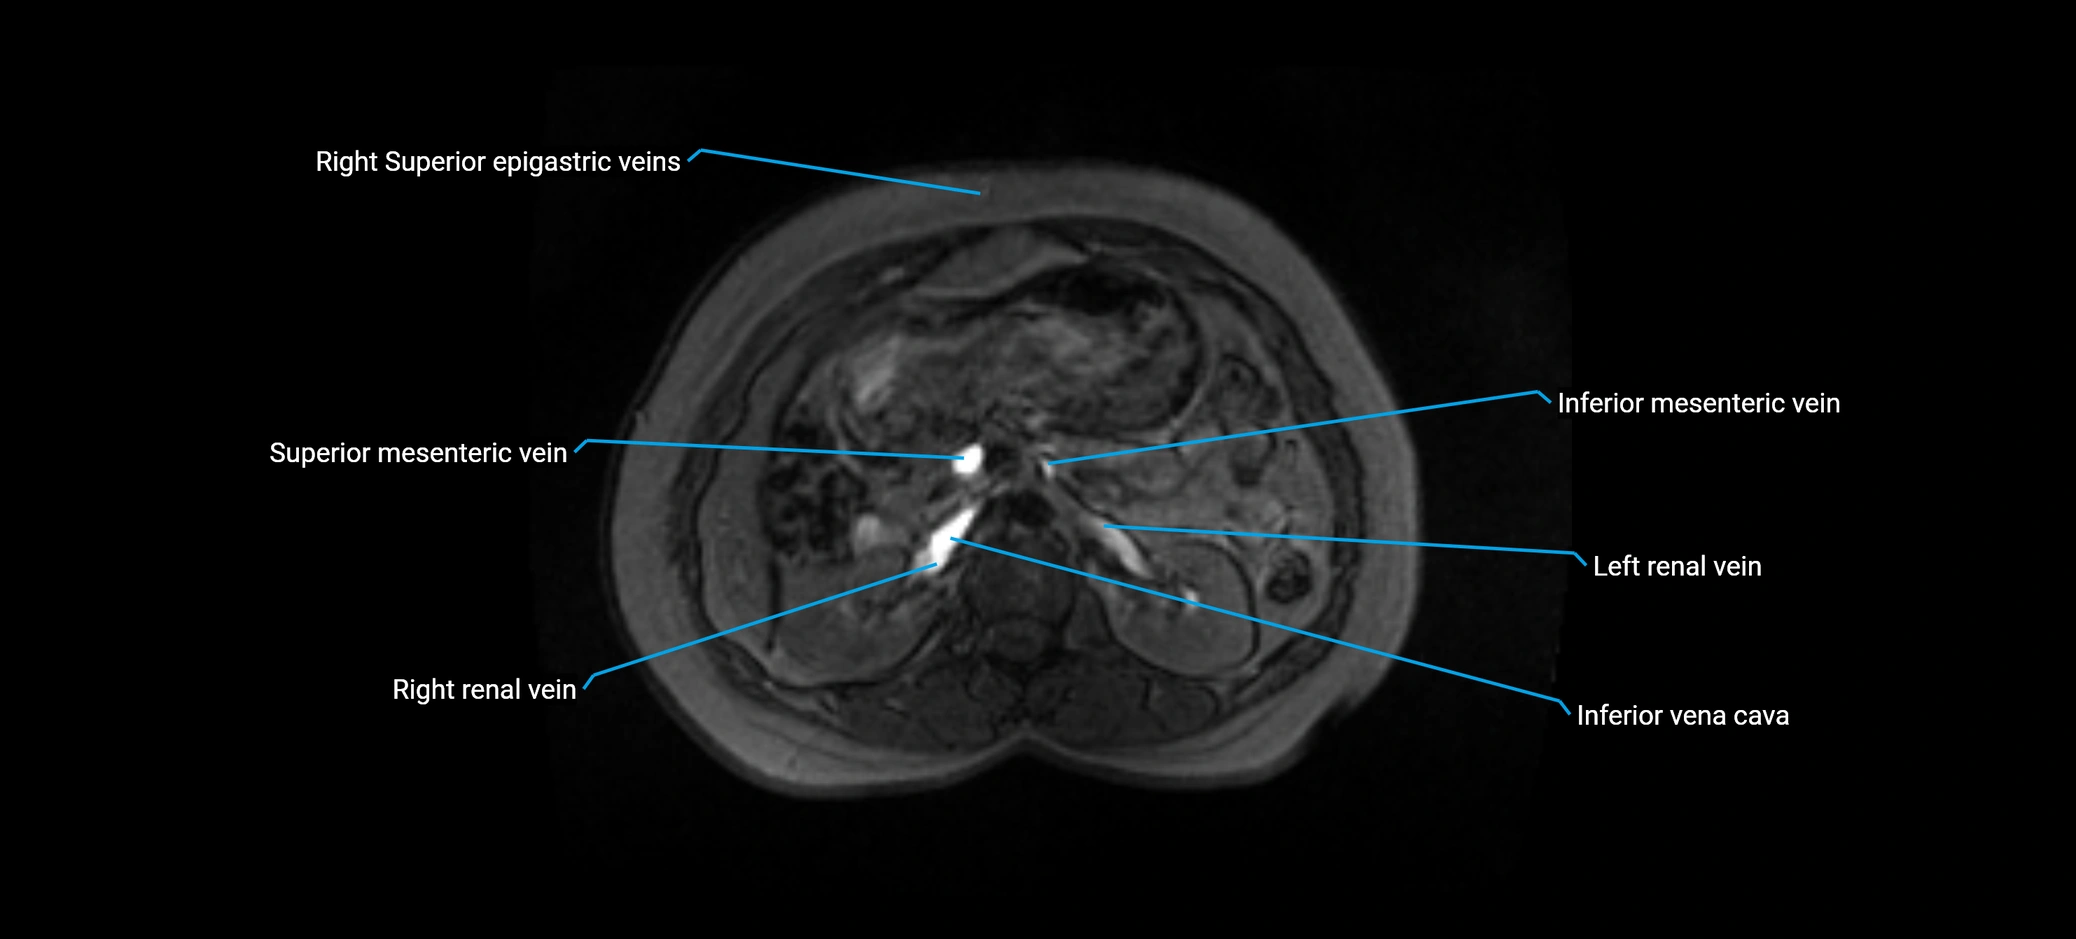

MRI image

image